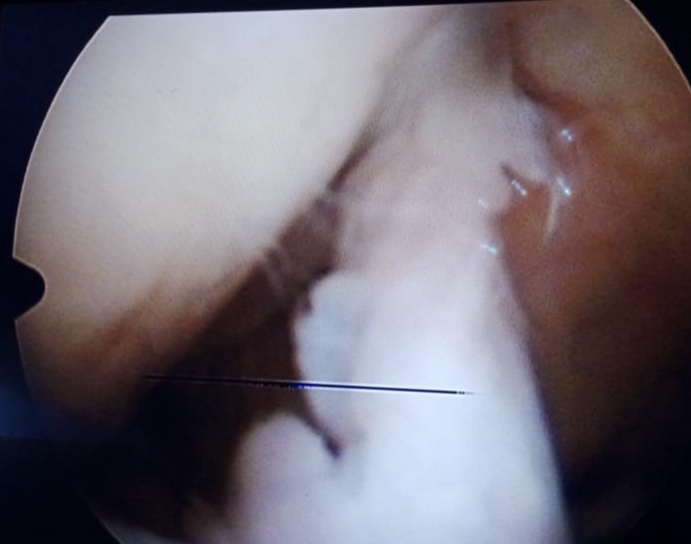

Warning: Graphic Content

The following section contains graphic images of surgical procedures. These images are intended for educational purposes and may be disturbing to some viewers. Viewer discretion is advised.

Surgeries